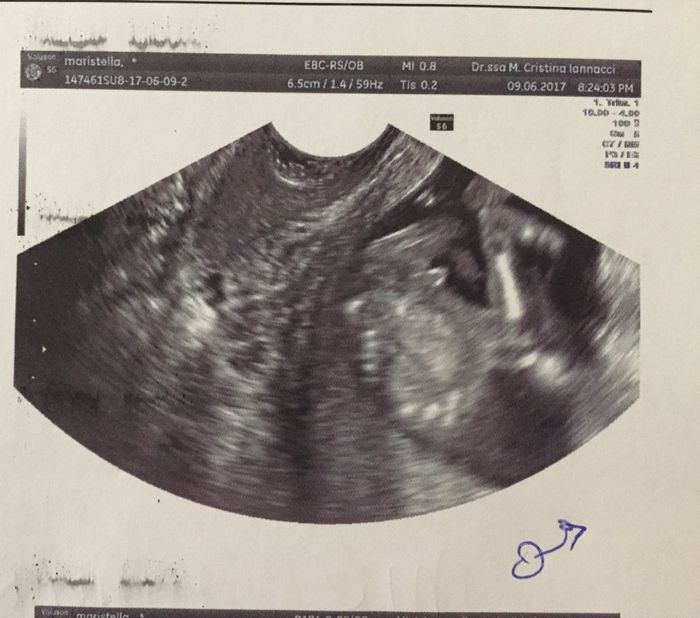

14+1 ecografia

Da Mari , Il 9 Giugno 2017 alle 20:01

Ciao ragazze siamo appena tornati del l'ecografia e si è fatto vedere proprio bene è un maschietto proprio come immaginavamo 😍😍😍...